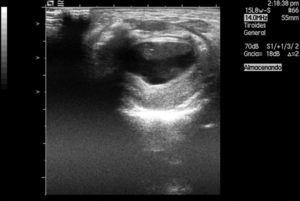

Una recién nacida a término mediante parto eutócico con test de Apgar 9-10, reanimación tipo I y 3.300 g de peso presentó a la exploración neonatal inmediata una masa sublingual de consistencia blanda, de aproximadamente 3 cm de diámetro. La paciente no tenía asociadas otras malformaciones. La masa no había sido diagnosticada durante las exploraciones prenatales y el embarazo había transcurrido con normalidad. No presentaba dificultad respiratoria ni alteraciones en la deglución. Se le realizó una ecografía en la que se visualizó una lesión quística compleja con contenido ecogénico y aglomerados en su interior, compatible con quiste dermoide (fig. 1). La paciente ingresó a los 15 días de vida para la extirpación quirúrgica de la lesión. Se realizó una quistectomía sublingual total, con marsupialización del lecho quístico y extracción íntegra del quiste (fig. 2). En las primeras horas tras la cirugía inicia tolerancia oral con lactancia materna sin incidencias. Al sexto día del postoperatorio la paciente fue dada de alta hospitalaria con control ambulatorio.

Figura 1. Lesión quística compleja con contenido en su interior, que ecográficamente sugería un quiste dermoide.